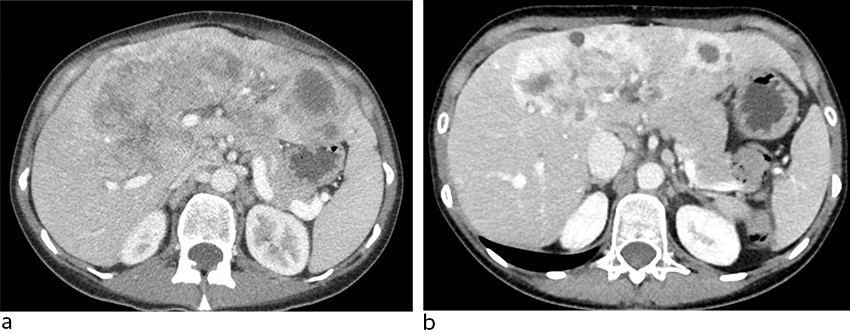

En tidligere frisk lite-røykende kvinne i 30-årene oppsøkte lege fordi hun følte seg sliten og hadde smerter i øvre del av buken. Hun ble utredet med blant annet CT abdomen, som viste multiple metastasesuspekte lesjoner opptil 12 cm i diameter i lever og forstørrede lymfeknuter i abdomen (figur 1a). Biopsi fra lever viste adenokarsinom. MR lever sannsynliggjorde diagnosen kolangiokarsinom med affeksjon av nesten alle leversegmenter.

CT-bilder tatt etter fem ukers behandling med entrektinib viste tydelig respons. Store konfluerende tumormasser sentralt i leveren var minket til 9,8 cm fra 11,7 cm før start av entrektinib, og en metastase i venstre leverlapp hadde blitt redusert fra 7,2 cm til 4,9 cm (figur 1b). Det var også tilbakegang av ascites.